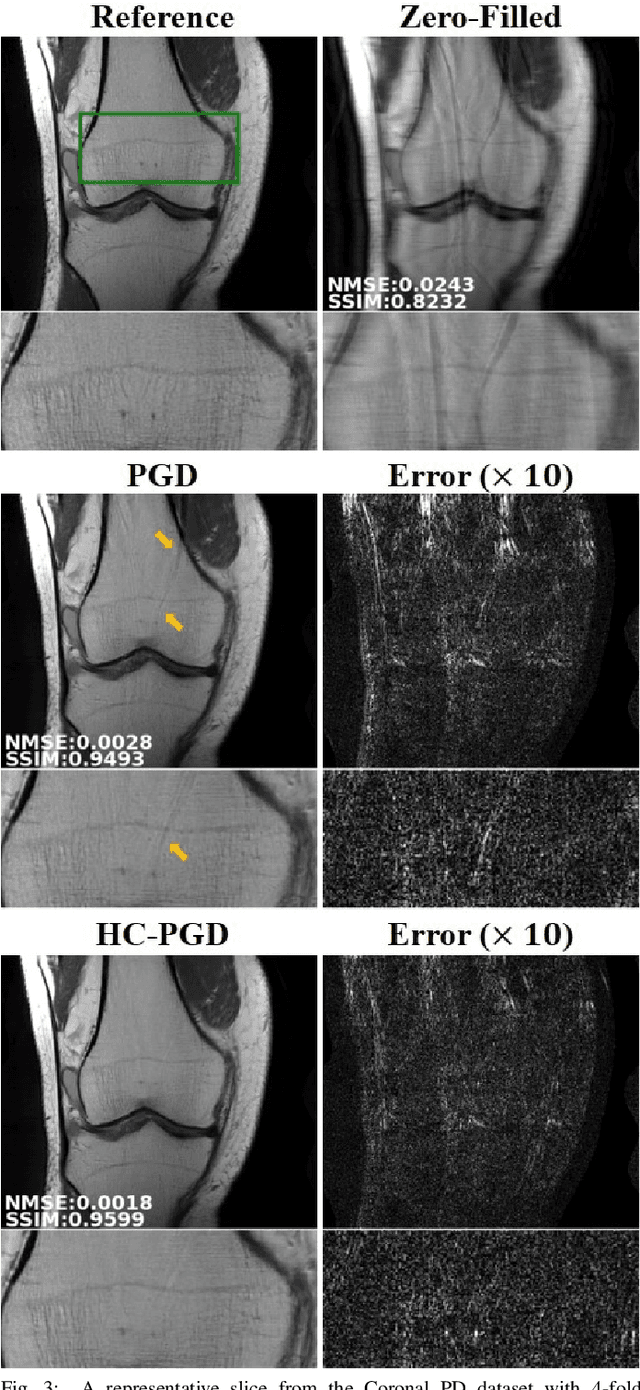

Abstract:Inverse problems in medical imaging applications incorporate domain-specific knowledge about the forward encoding operator in a regularized reconstruction framework. Recently physics-driven deep learning (DL) methods have been proposed to use neural networks for data-driven regularization. These methods unroll iterative optimization algorithms to solve the inverse problem objective function, by alternating between domain-specific data consistency and data-driven regularization via neural networks. The whole unrolled network is then trained end-to-end to learn the parameters of the network. Due to simplicity of data consistency updates with gradient descent steps, proximal gradient descent (PGD) is a common approach to unroll physics-driven DL reconstruction methods. However, PGD methods have slow convergence rates, necessitating a higher number of unrolled iterations, leading to memory issues in training and slower reconstruction times in testing. Inspired by efficient variants of PGD methods that use a history of the previous iterates, we propose a history-cognizant unrolling of the optimization algorithm with dense connections across iterations for improved performance. In our approach, the gradient descent steps are calculated at a trainable combination of the outputs of all the previous regularization units. We also apply this idea to unrolling variable splitting methods with quadratic relaxation. Our results in reconstruction of the fastMRI knee dataset show that the proposed history-cognizant approach reduces residual aliasing artifacts compared to its conventional unrolled counterpart without requiring extra computational power or increasing reconstruction time.